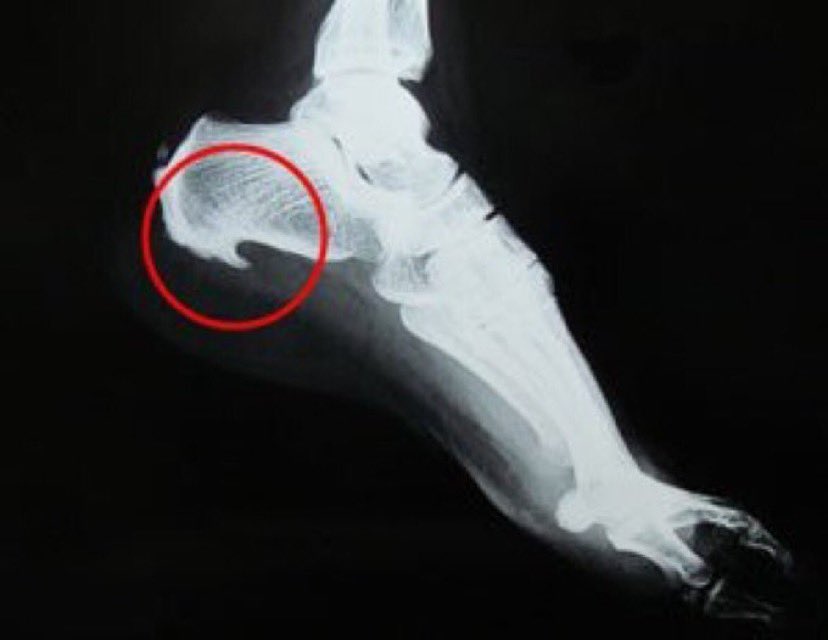

#شوكة_القدم

♦️عبارة عن التهابات في الأنسجة الرخوية يحدث بعدها ترسب للكالسيوم ليكون هذه الشوكة

♦️وهي استجابة الجسم للتوتر والضغط الواقعين على أربطة وأوتار القدم

♦️مثال: عندما تصاب بالتهاب اللفافة الأخمصية ، يستجيب جسمك للإجهاد عن طريق خلق نتوء في الكعب و اللي تكون الشوكة